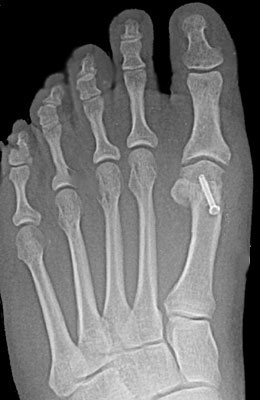

In this procedure (also known as an “Austin Bunionectomy), a cut in the bone was made, and the bone was shifted to realign the joint. A screw was placed to hold this new alignment in place. Notice the improved alignment of the great toe joint.

Before

Austin Bunionectomy with Akin Procedure before

After

Austin Bunionectomy with Akin Procedure after

Austin Bunionectomy with Akin Procedure

In the Austin procedure, a cut in the bone was made, and the bone was shifted to realign the joint. A screw was placed to hold this new alignment in place. Notice the improved alignment of the great toe joint. The Akin procedure involves making a bone cut in the toe bone and is used if there is a drift of the great toe towards the 2nd toe.